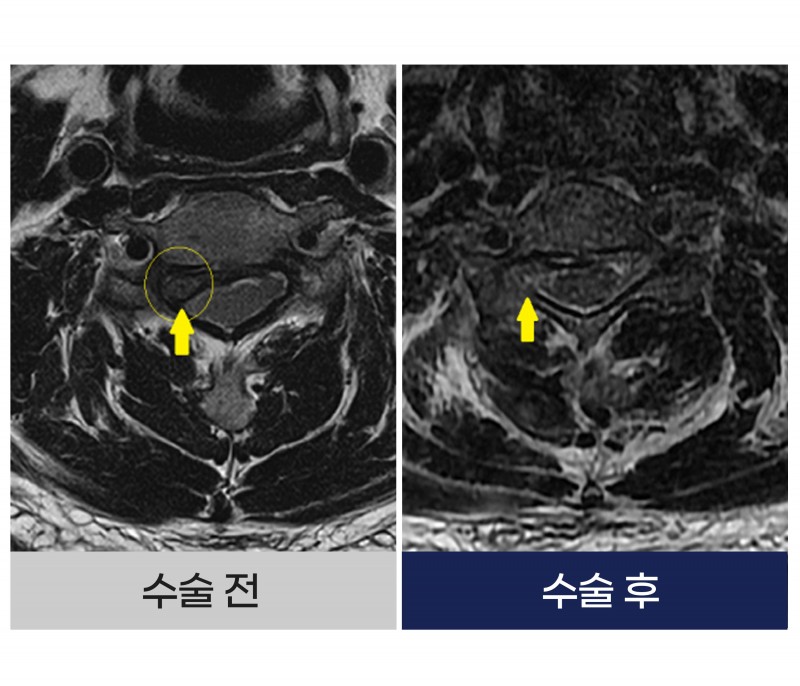

■ Before (수술 전)

✔ 목 통증과 팔 저림 지속

✔ 팔꿈치 통증으로 오인하여 장기간 치료 진행

수개월간 팔꿈치 통증(테니스 엘보)으로 정형외과 치료 시행

체외충격파, 주사치료 등에도 불구하고 호전 없음

시간이 지날수록 팔 저림 및 통증 악화와 일상생활 불편 증가

단순 팔꿈치 질환으로 생각했지만 실제 원인은 경추 디스크로 인한 신경 압박

■ After (수술 후)

✔ 정확한 원인 진단 → 경추 디스크 확인

✔ 경추 내시경 수술 시행

신경을 압박하던 디스크 제거해

팔 저림과 통증이 호전되었고 일상생활로 원활한 복귀

잘못된 진단으로 지연되었던 치료를 정확한 진단 후 빠른 회복